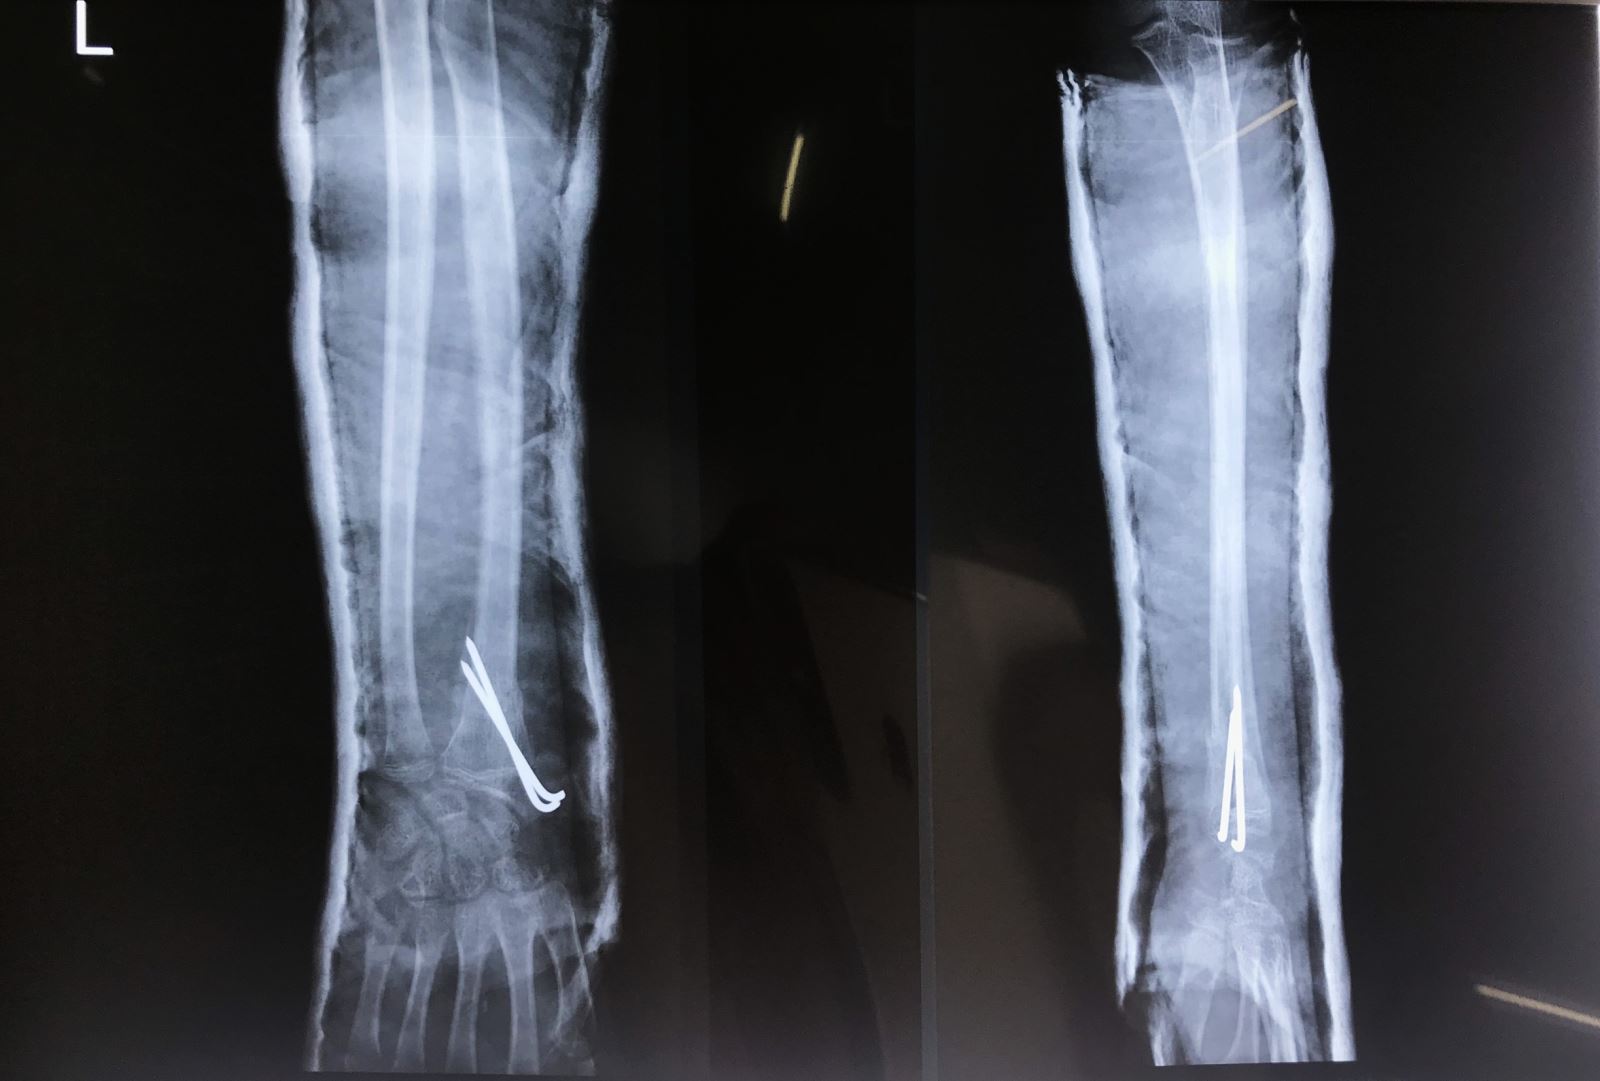

2. Phẫu thuật

Điều trị phẩu thuật khi bảo tồn thất bại, gãy hở

- Nắn kín và xuyên đinh qua da dưới màn hình tăng sáng

- Mổ hở nắn chỉnh và cố định bên trong: Nắn kín thất bại